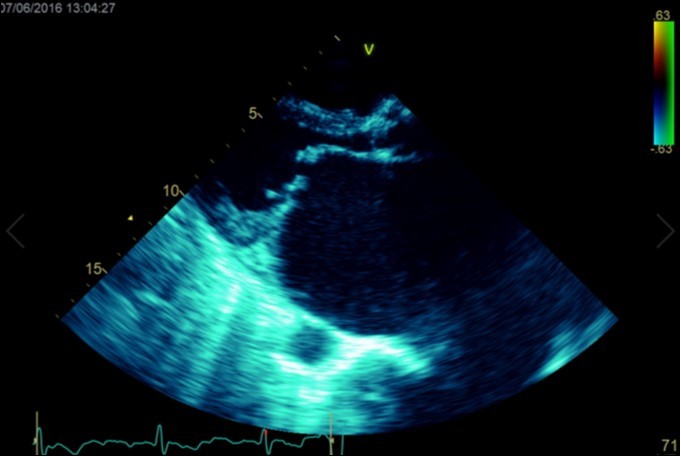

A dramatically dilated left atrium was seen on a TTE (see Figure 2a, Figure 2b, Figure 2c, and Figure 2d). Severe mitral stenosis with associated regurgitation was evident, with a mean gradient across the valve of 11mmHg and a hyperdynamic left ventricle. The left atrial volume measured by Simpson’s biplane method (see Figure 2c) was 2108mL, or 1548.5 ml/m2, based on height 1.55 metres and weight 44 Kg. Normal left atrial volume in a woman is 16 - 34 ml/m21. The computed tomography scan (CT) chest AP view (see Figure 3) is also shown.

Figure 2a.Transthoracic echocardiogram Apical 4C view. Findings include severely enlarged left atrium, severe mitral stenosis with associated regurgitation, a mean gradient across the valve of 11mmHg with a hyperdynamic left ventricle

Figure 2b.Transthoracic echocardiogram Parasternal long axis view. Findings include severe mitral stenosis (‘hockey-stick’ appearance to mitral valves), raised left atrial pressure (interatrial septum fixed and bowed to right)

Massive left atrial dilatation is a recognized phenomenon in chronic mitral stenosis, and is considered by some to be protective against the development of pulmonary oedema in mitral regurgitation 2. Left atrial dilatation to this extent is not usually seen in living patients, however. The largest described left atrium was 3000 ml at autopsy, with another measuring 1760 ml at autopsy in 19313. Other reports in living patients include a left atrium that was estimated at approximately 2000ml on magnetic resonance imaging 4.The more precise measurements for the left atrial size we recorded on cardiac ultrasound have not been described previously. Considering the size of the left atrium, it is surprising that the mean gradient across the mitral valve was only 11mmHg. Although this is certainly severe, it could be expected that a gradient would be higher based on the severity of the left atrial dilation. We hypothesize that the gradient may have been greater previously, however the massive dilation of the left atrium may have subsequently led to a dilation of the mitral annulus, leading to an improvement in the mitral valve effective orifice area, and hence a reduction in the severity of the mean mitral valve gradient.